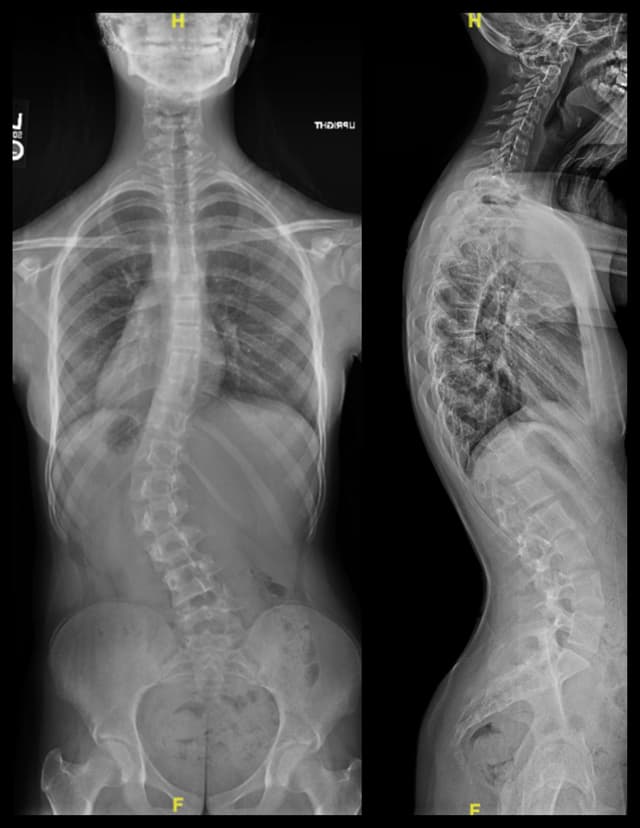

Posterior Spinal Fusion for Scoliosis

Imaging

Pre-op